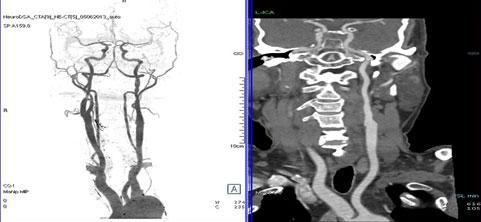

二、多層螺旋CT頭頸部及體部血管成像技術:

該機掃描覆蓋範圍廣、時間短,多種後處理分析軟件能顯示各血管細小分支,可以清晰顯示動脈瘤、動脈夾層、血管畸形、血管狹窄及動脈粥樣硬化斑塊等,适用于頭頸部血管成像、肺動脈成像、胸腹部血管成像及四肢血管成像。

1.顱腦血管成像:

動脈瘤

2、頸部血管成像